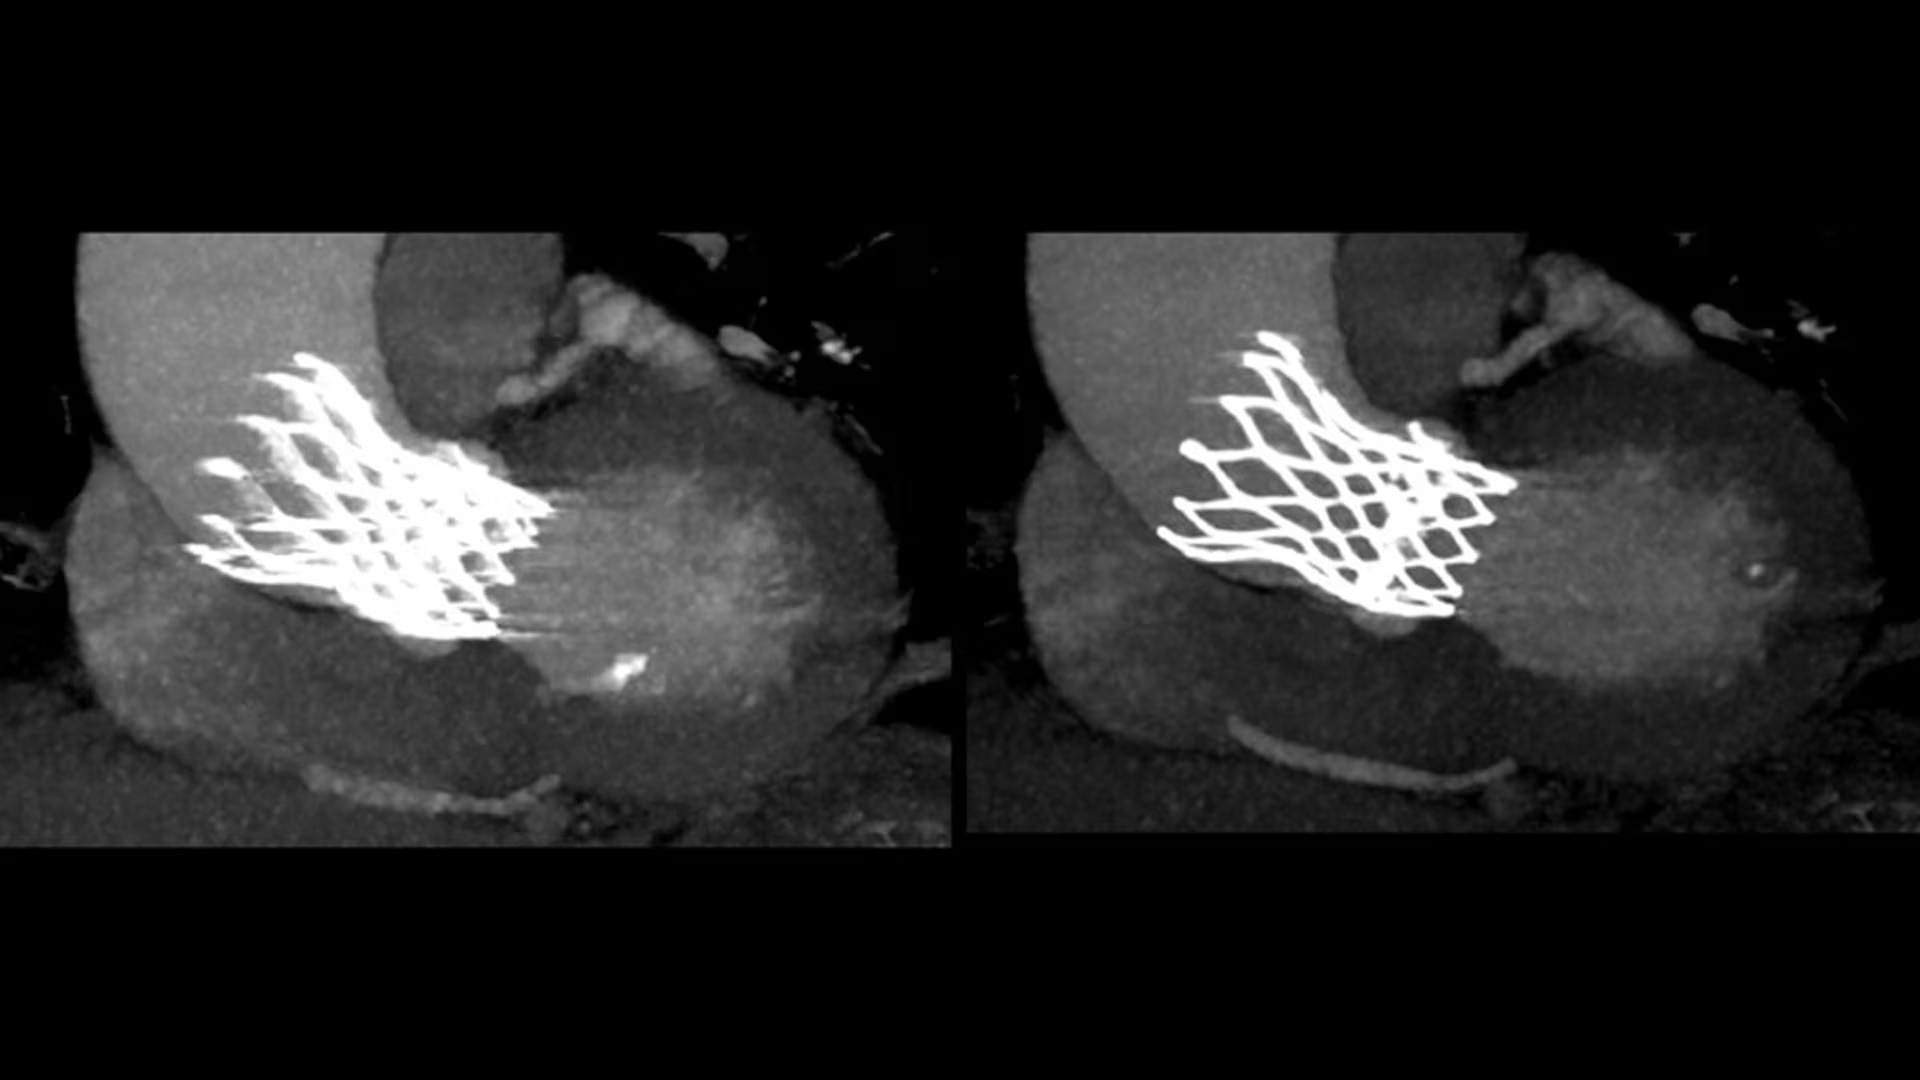

SnapShot Freeze 2

Intelligent and automated whole-heart motion correction for enhanced Cardiac CT imaging.

Motion correction

6x reduction in motion artifacts1

Temporal resolution

19.5 msec effective temporal resolution at 0.23s/rotation gantry speed2

Automated

Whole-heart motion correction

1. As demonstrated in mechanical and mathematical cardiac phantom testing

2. SnapShot Freeze 2, in conjunction with 0.23 s/rotation gantry speed, provides a reduction in coronary motion artifacts that is equivalent to a 0.039 s/rotation equivalent gantry rotation speed with effective temporal resolution of 19.5 msec. As demonstrated in phantom testing using a commercially available motion phantom and also with a mathematical cardiac phantom with linear motion of variable velocity. The 0.039 s/rotation images are modeled without application of SnapShot Freeze 2. Results may vary in clinical applications.